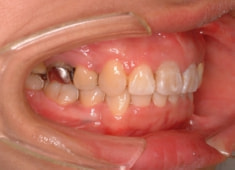

治療前